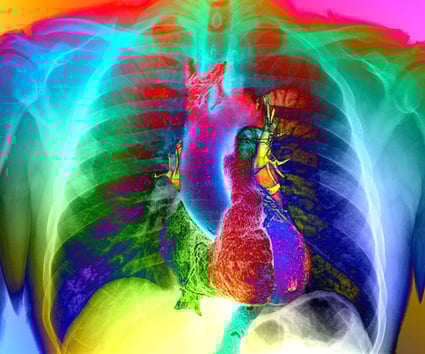

L’essoufflement est un symptôme fréquent du Covid long, alors que les tests pulmonaires courants – y compris les radiographies pulmonaires, les tomodensitogrammes et les tests fonctionnels – sont parfois redevenus normaux.

Des analyses détaillées de leur fonction pulmonaire ont indiqué que la plupart des patients absorbaient l'oxygène moins efficacement que les personnes en bonne santé, même si la structure de leurs poumons semblait normale.

Cependant, une étude très récente (01 2022) en imagerie RMN (au xénon hyperpolarisé), pilotée par des chercheurs du Département de radiologie, d'Oxford University Hospitals NHS Trust, semble indiquer que le virus serait à l'origine de lésions microscopiques au niveau des poumons.